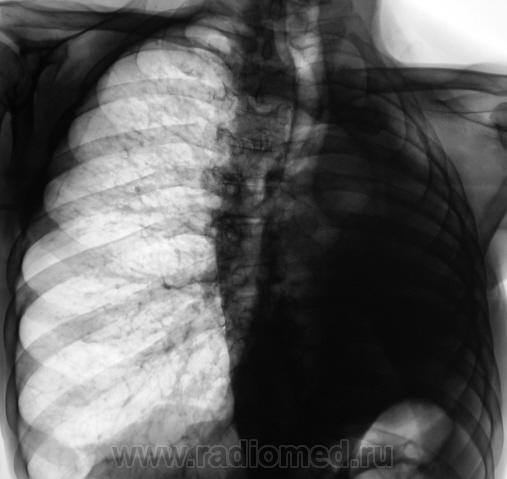

Повторили и "прямую", и произвели томограммы.

.....При гематогенном генезе подострого диссеминированого туберкулеза однотипная очаговая диссеминация локализуется в верхних и кортикальных отделах легких....

Очаги крупноваты для диссеминированного Tbc.

Так не миллиарный же, а просто - дисеминированый...если так посмотреть на вопрос?

Мы тоже склонились в пользу диссеминированного.

Очаги будут мономорфны только при свежей диссеминации, а в динамике какому очагу как повезет:)

Важно то, что мы "посылальщика" упаковали. Выставлен диссеминированный туберкулёз.